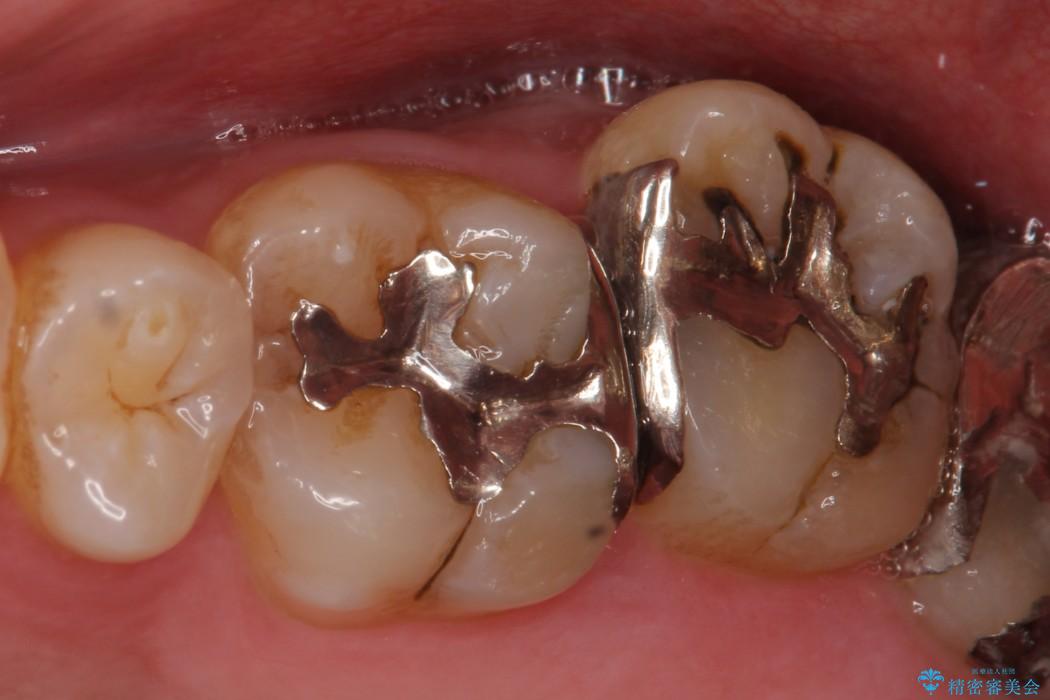

左上の他院で治療した銀歯の見た目が気になり白いものへ変えたいとの主訴で来院されました。

古い詰め物を外し、白く審美性の高いセラミックインレーにて再治療を行うこととしました。

保険で治療した銀歯は、経年劣化で詰め物のふちが欠けたり、適合が悪くなり詰め物の下など目に見えない部分の虫歯の原因となることがあります。また、金属のため口にするものの熱の影響を受けやすく成分が溶けやすくなったり、変形してしまうことがあります。